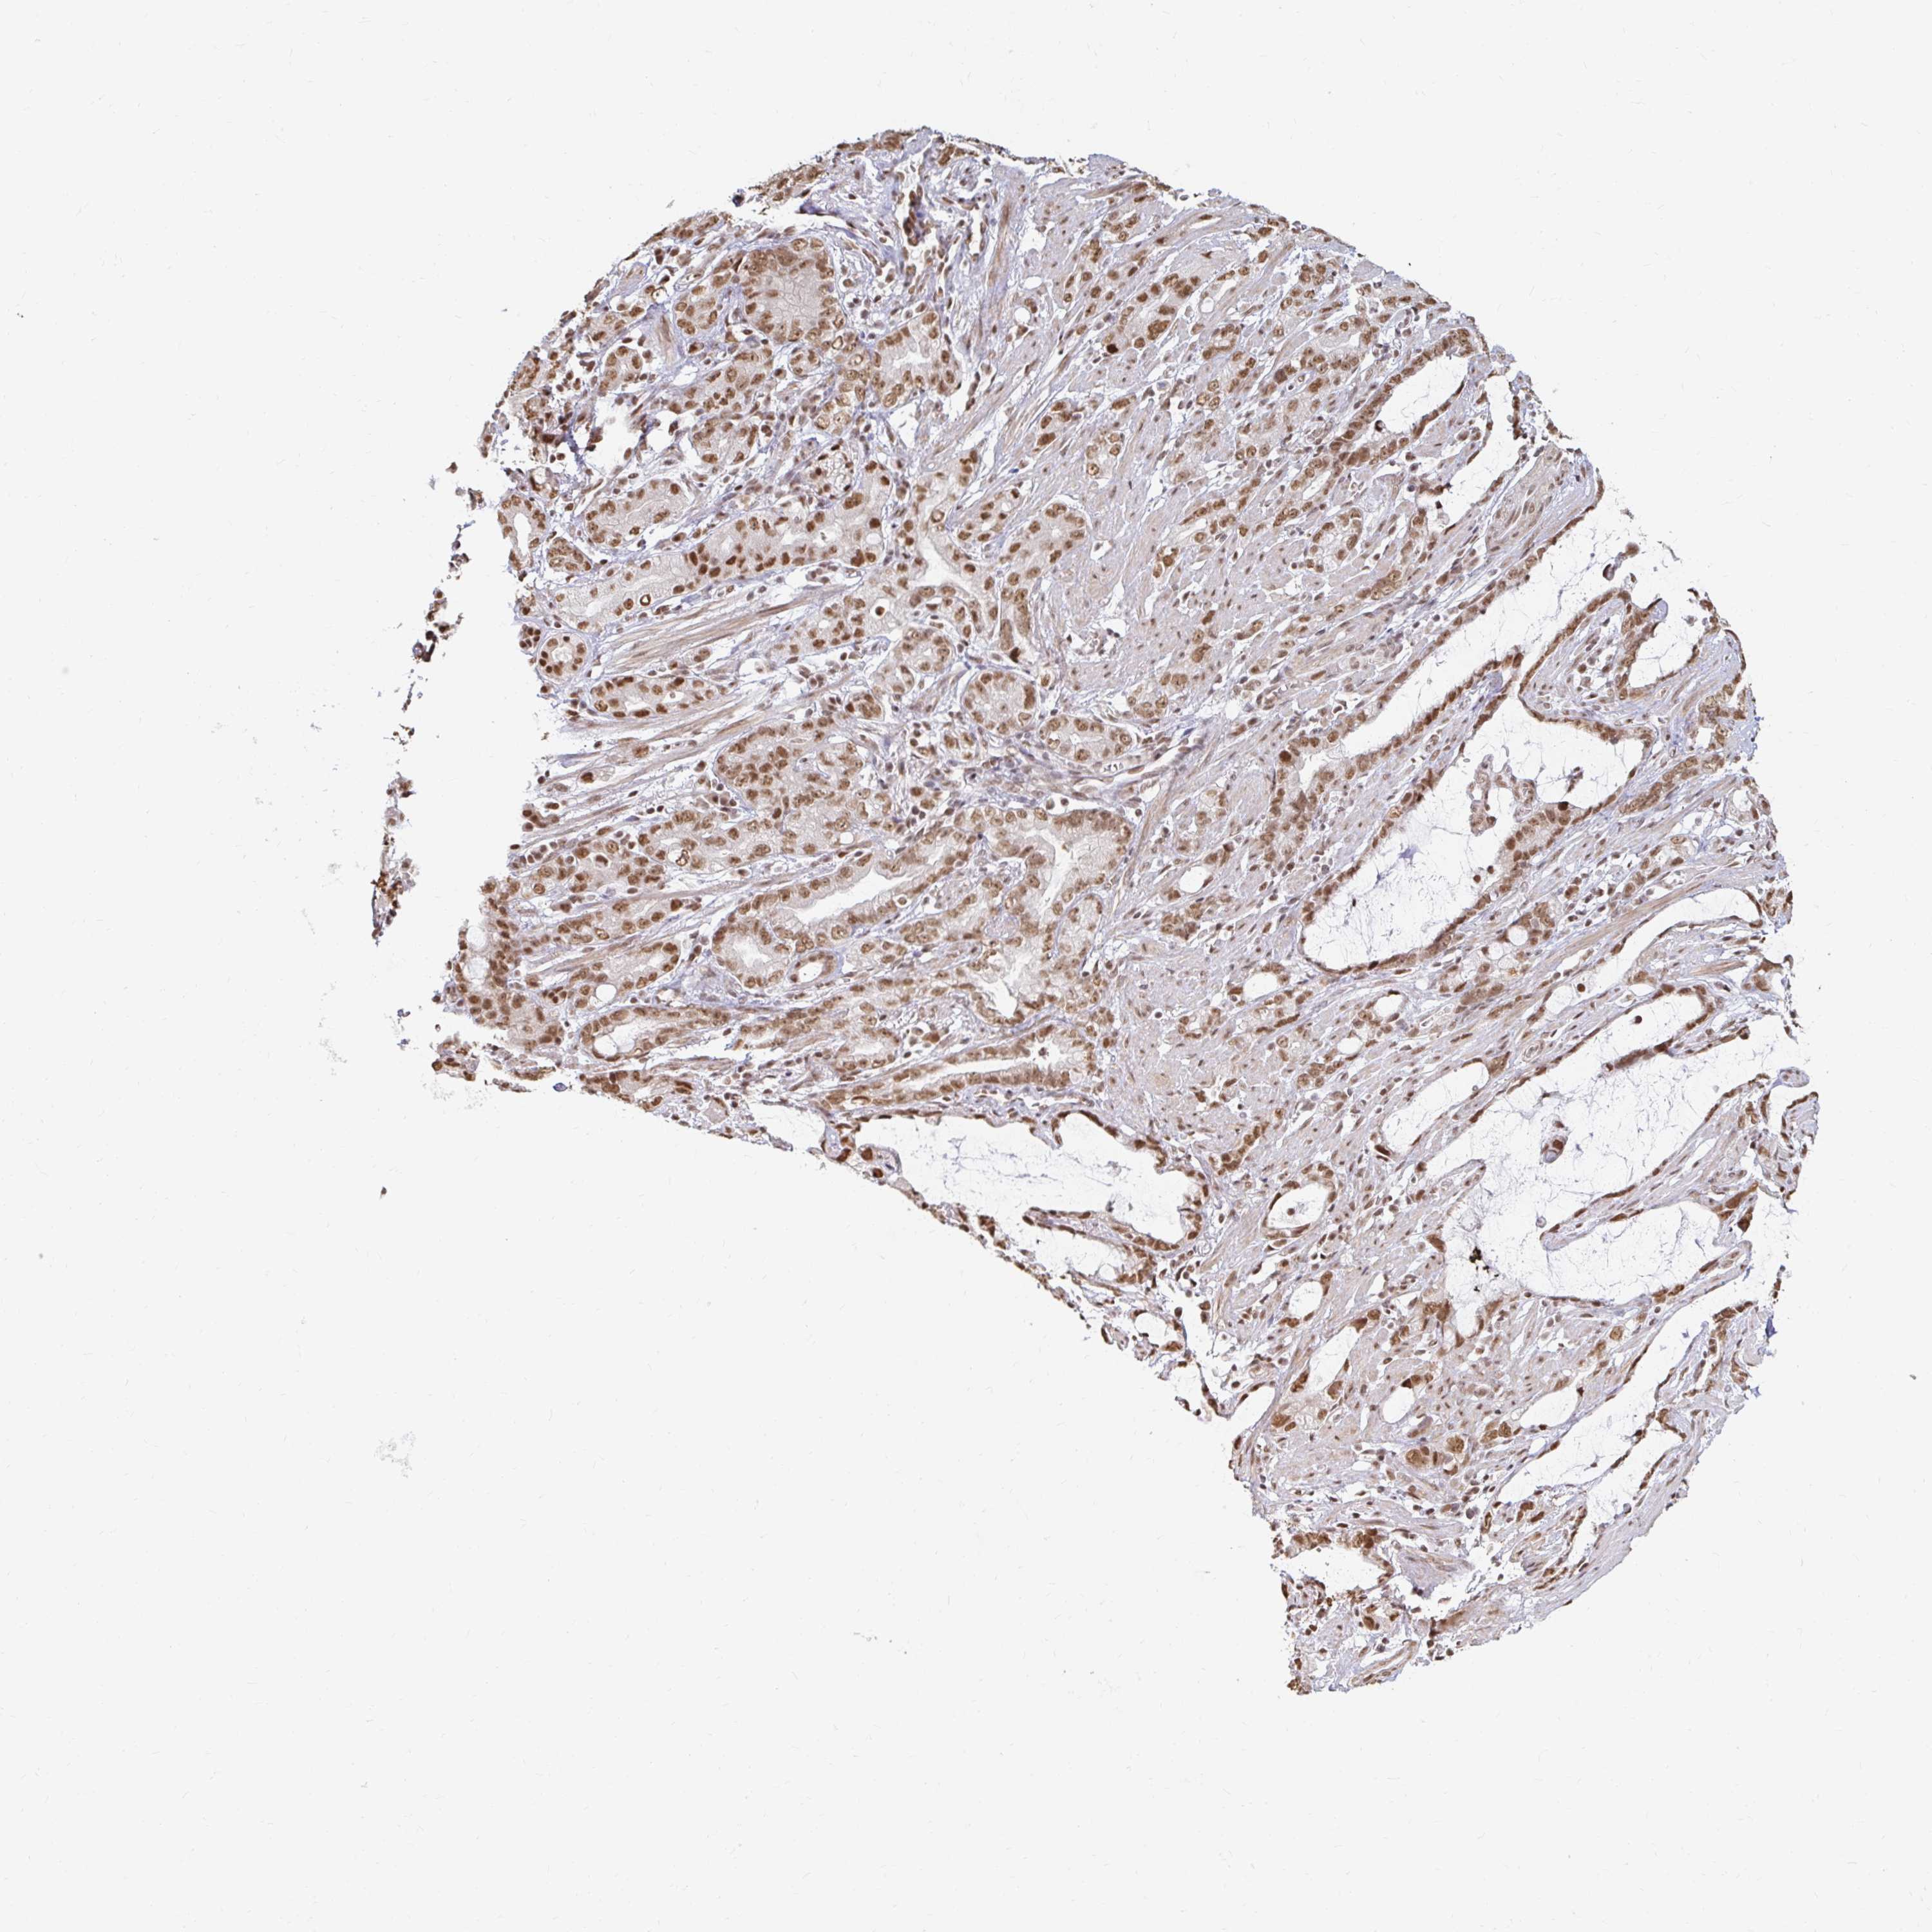

STOMACH CANCER - Protein expressioni

A mouse-over function shows sample information and annotation data. Click on an image to view it in a full screen mode. Samples can be filtered based on level of antibody staining by selecting one or several of the following categories: high, medium, low and not detected. The assay and annotation is described here.

Note that samples used for immunohistochemistry by the Human Protein Atlas do not correspond to samples in the TCGA dataset.

Antibody stainingi

Antibody staining in the annotated cell types in the current human tissue is reported as not detected, low, medium, or high, based on conventional immunohistochemistry profiling in selected tissues. This score is based on the combination of the staining intensity and fraction of stained cells.

Each image is clickable and will lead to virtual microscopy that enables deeper exploration of all samples and also displays staining intensity scores, fraction scores and subcellular localization as well as patient and tissue information for each sample.

Antibody HPA041057

Antibody HPA058707

Antibody CAB011532

Staining

High

Medium

Low

Not detected

Intensity

Strong

Moderate

Weak

Negative

Quantity

>75%

75%-25%

<25%

None

Location

Nuclear

Cytoplasmic/membranous

Cytoplasmic/membranous,nuclear

Adenocarcinoma, NOS

Adenocarcinoma, High grade